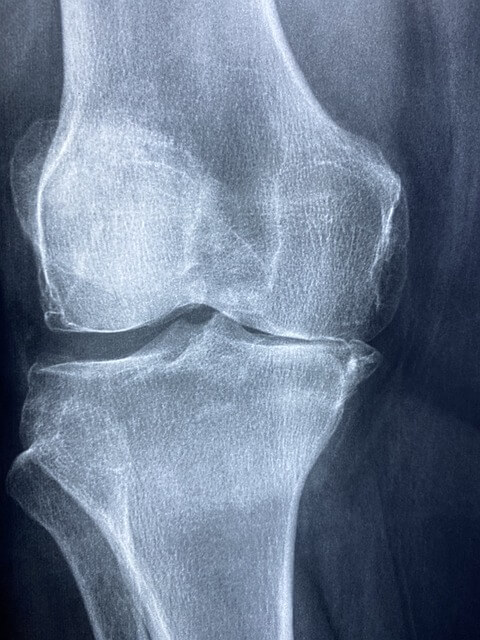

Arthritis in dogs is most commonly checked through x rays, which provide valuable insights into their condition.